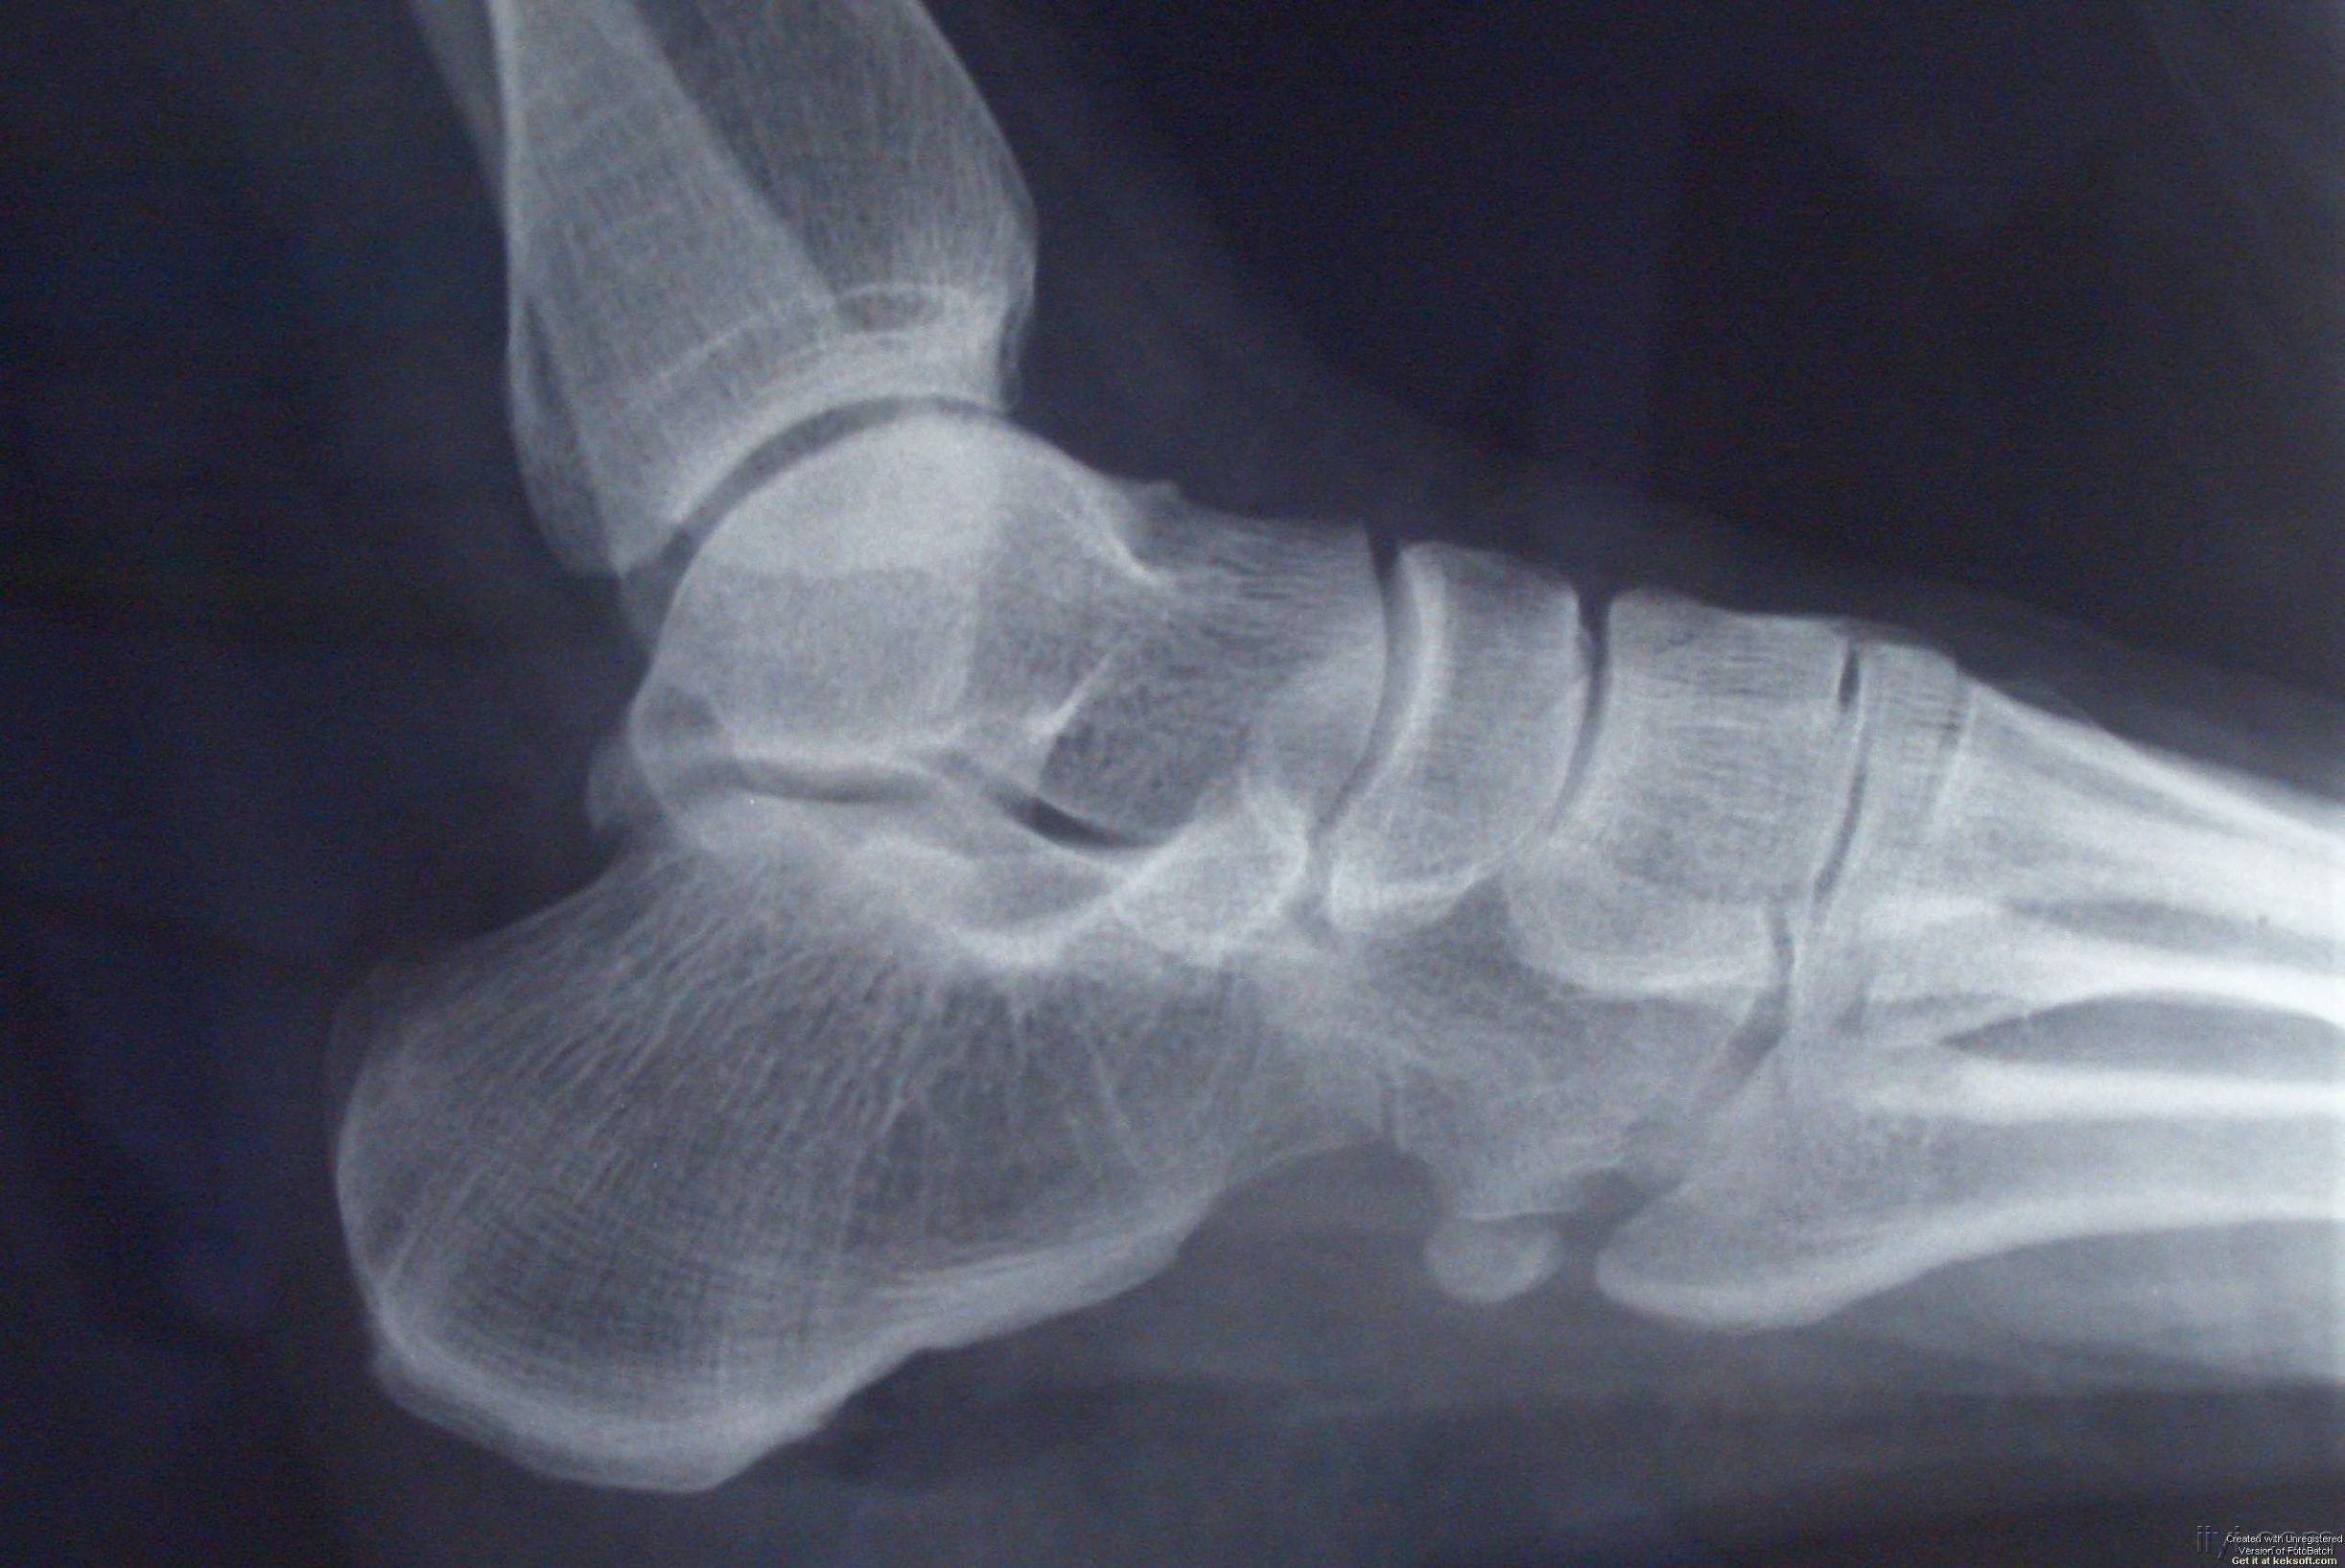

发生跟骨疼,若去拍X光片,可以发现跟骨结节处有大小不一的骨疣形成,但这并不是导致疼痛的直接原因。只是这些隆起的骨疣,更容易使局部策划劳损,产生无菌性炎症。或因过度的牵拉引发足底筋膜炎,引起跟腱紧张,带来疼痛。